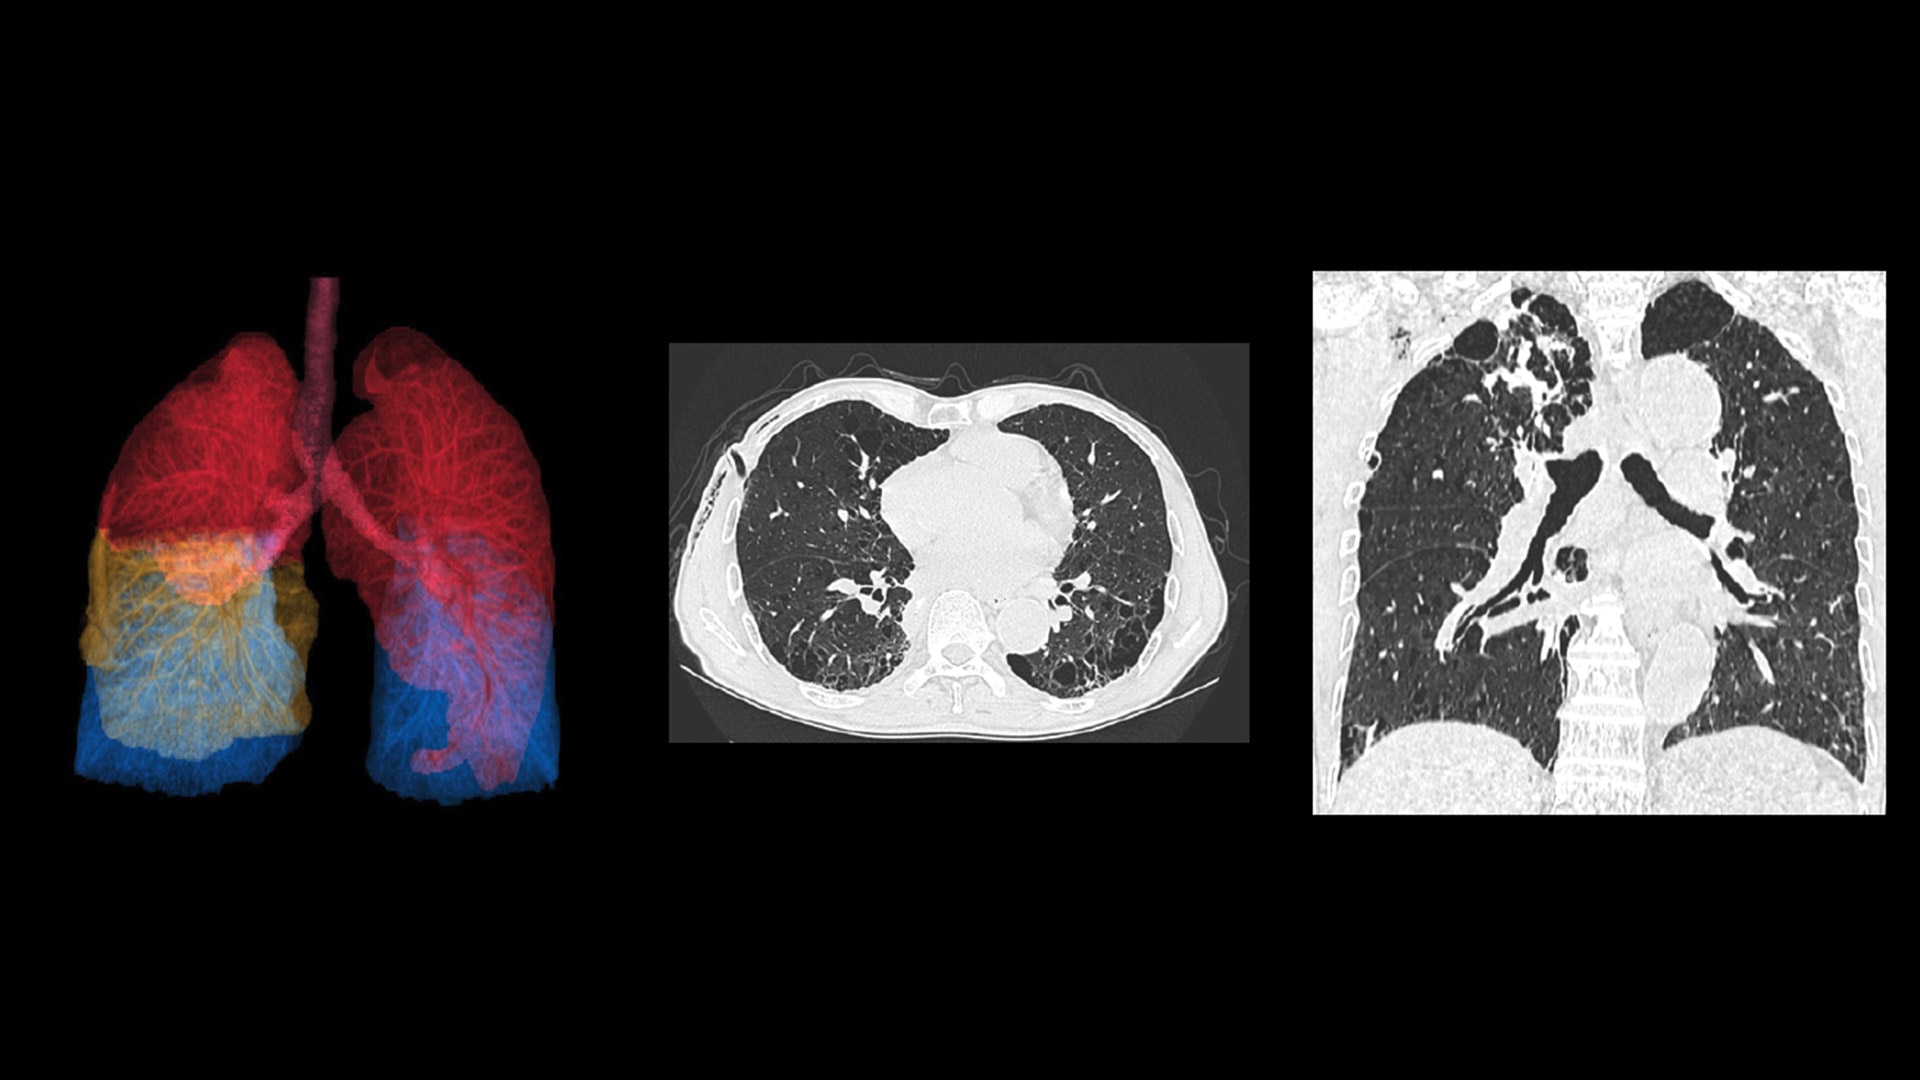

At the heart of Revolution Advance is a high-performance, reliable imaging chain with 42 kW of generator power, a 3.5 MHU X-ray tube and integrated detectors that reduce signal-to-noise by 20%2. This is paired with our smart, dose-reducing reconstruction applications like ASiR2, which can provide up to 40% lower dose while maintaining high image quality2.

When it comes to imaging more challenging cases, such as neuro, oncology or pediatric patients, VISR3. (Volumetric Image Space Reconstruction) reduces noise without impacting image resolution. This means less dose for the patient while maintaining the high-image quality you need for more accurate diagnoses.